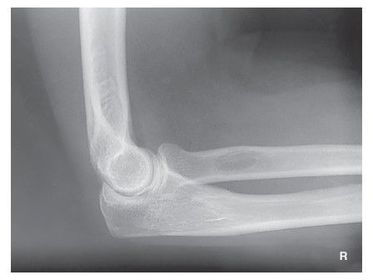

G. superimposed epicondyles of humerus I. trochlear sulcus J. trochlear notch K. outer ridges of capitulum and trochlea L. coronoid process of ulna M. radial head N. radial neck

a. outer ridges of capitulum and trochlea b. trochlear notch c. trochlear sulcus

1. trochlear sulcus 2. outer ridges of capitulum and trochlea 3. trochlear notch

AP Lateral Elbow 60-75 kVp 40 SID 10x12 IR nongrid CR @ midelbow joint MUST SEE 3 concentric arcs, olecranon process